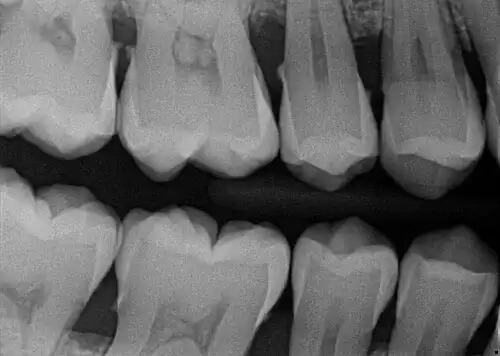

How to take a good dental x-ray is not only about proper technique... but actually understanding what you are looking for in the image is super important too!Are Dental X-Rays Safe?